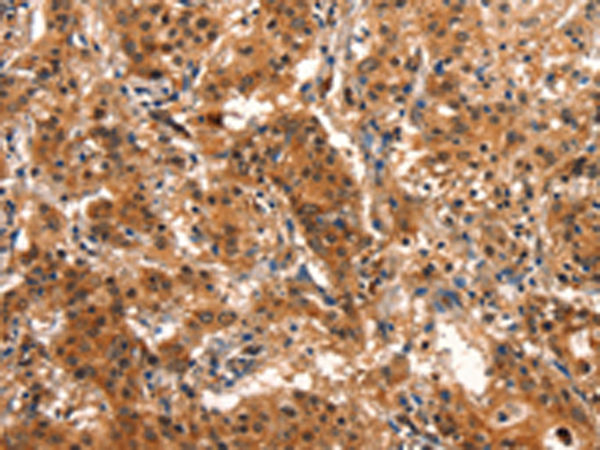

分类: 科研抗体货号: P11208别名: CAE; CAE1; CX50; CZP1; MP70; CTRCT1应用: IHC反应种属: Human, Mouse, Rat